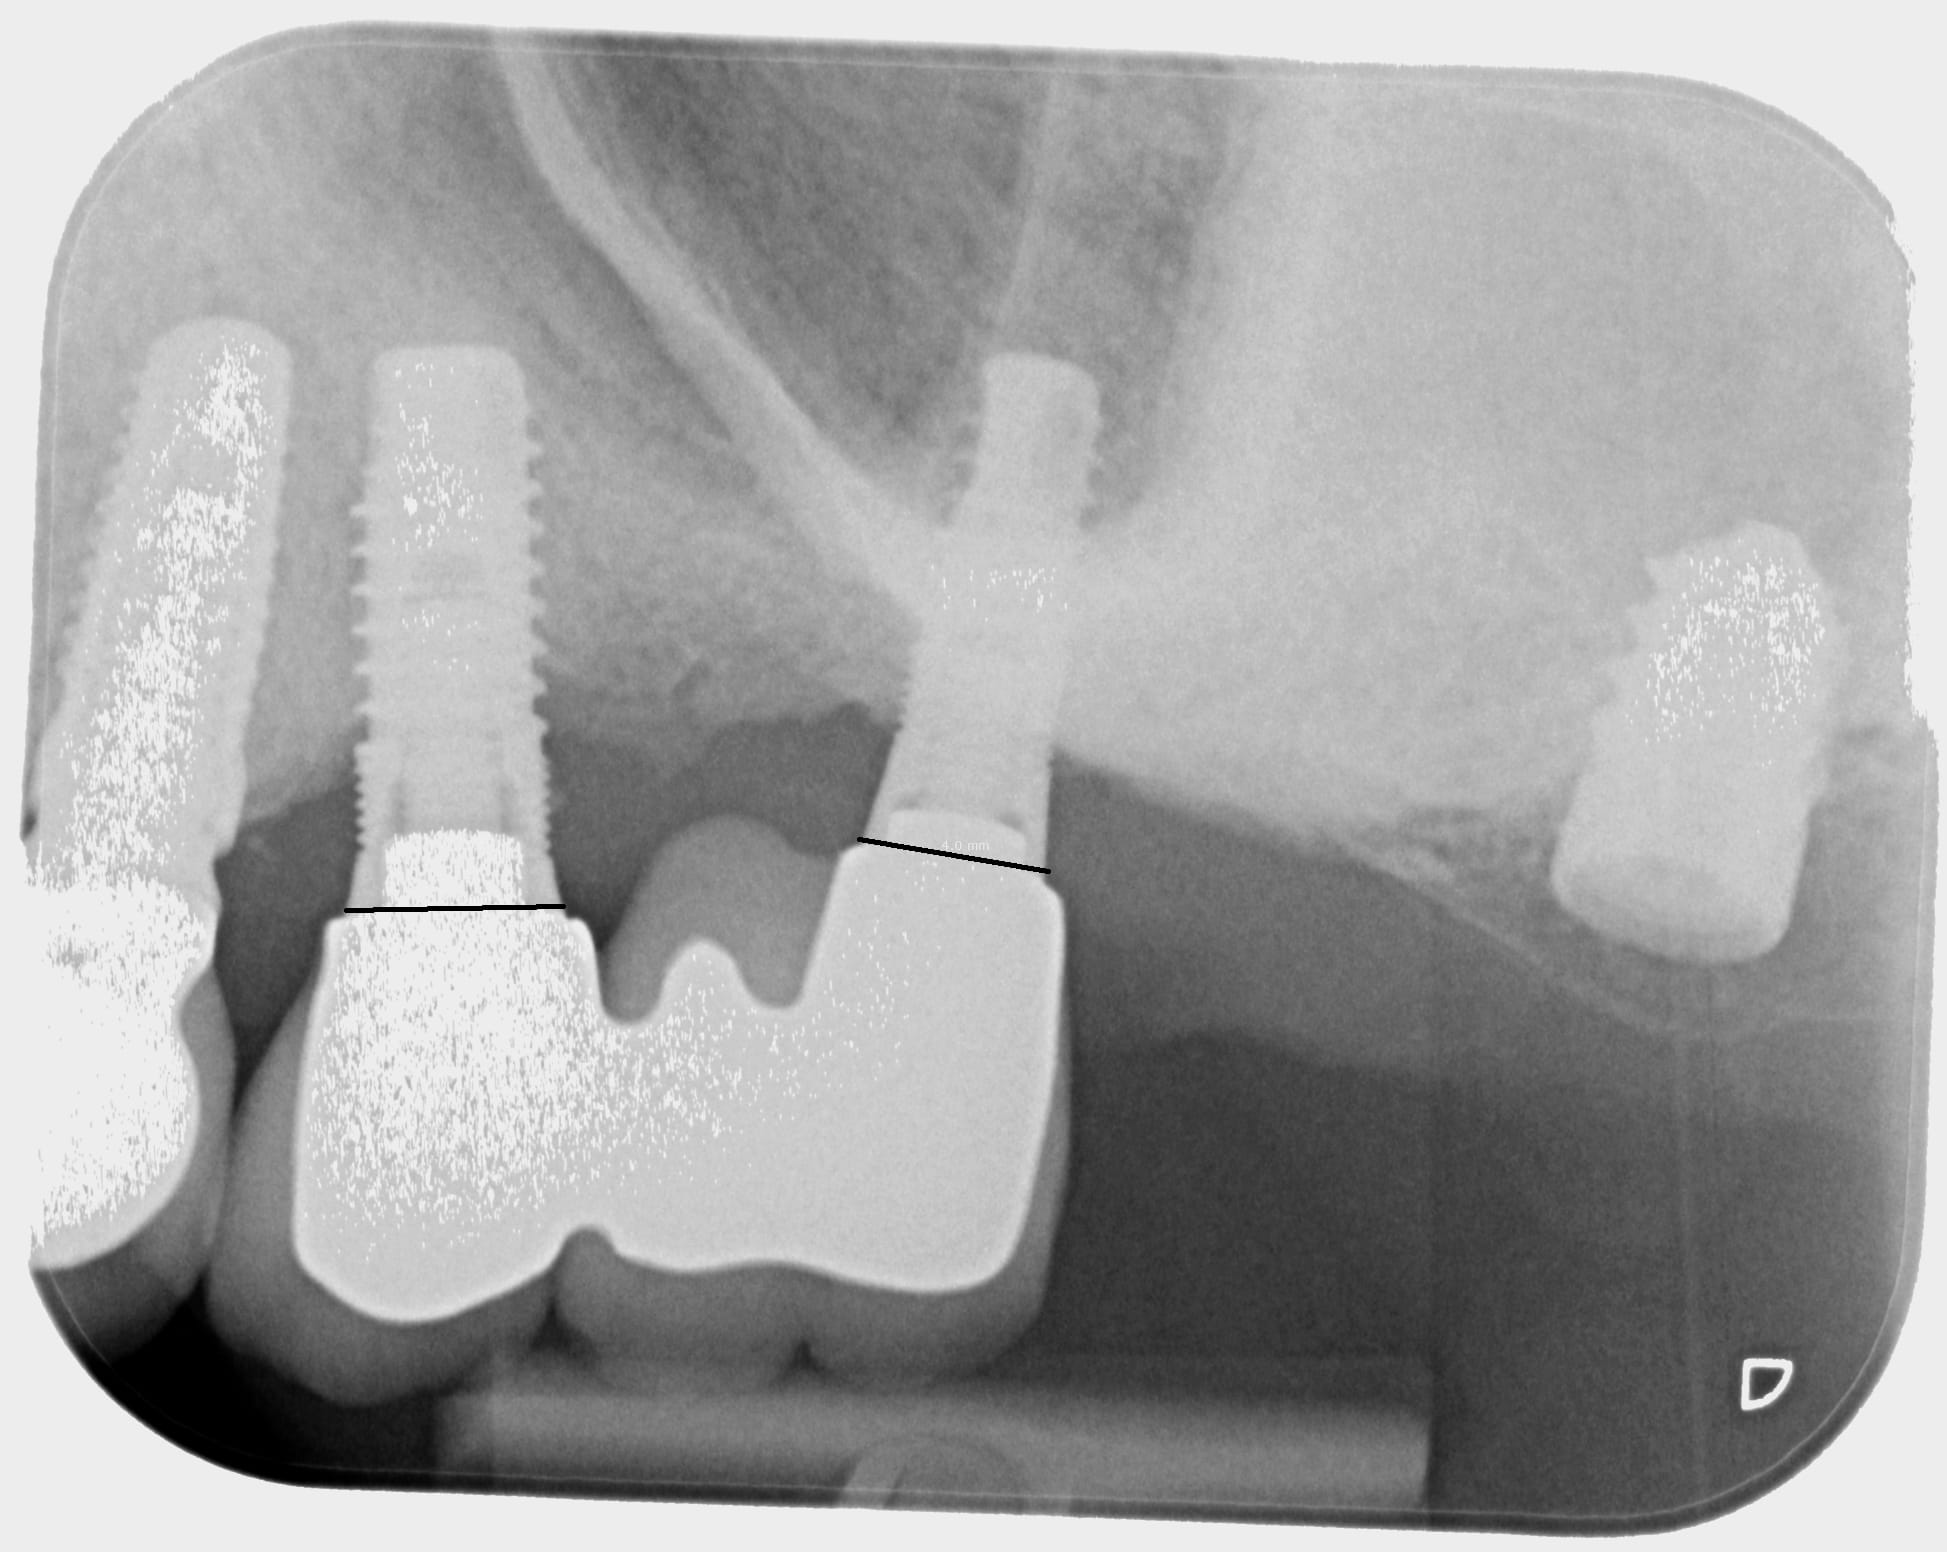

bonjour, cette fois ce serait pour identifier l'implant isolé en 27 si la radio le permet...

C'est justement le problème, ta radio très saturée mange beaucoup de détails au niveau de cet implant et pour l'instant je ne trouve rien....

ok je vais voir avec mon correspondant si il n'aurait pas une radio mieux définie..